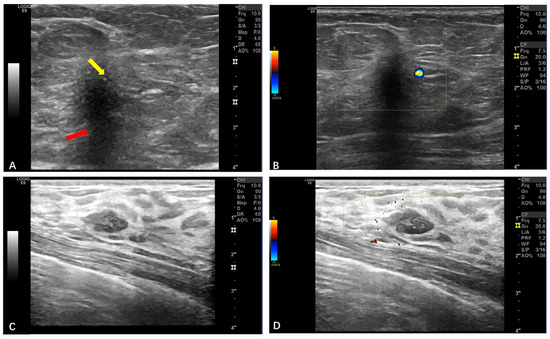

| Soft Tissue | Ultrasound (n = 26) | Well-circumscribed hypoechoic masses (n = 25, 96.1%); sparse blood flow. | Larger size (mean: 93 mm); rare irregular margins. |

| Breasts | Ultrasound (n = 5) | Irregular margins; a non-parallel orientation; posterior shadowing (BI-RADS 4B) (n = 4, 80%) | N/A (all benign) |